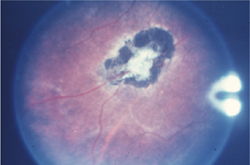

図6-3a 網膜血管腫

図6-3b 網膜血管腫(治療前)

血管腫より出血を認める。

図6-3c 網膜血管腫(治療後)

網膜光凝固斑を認める。